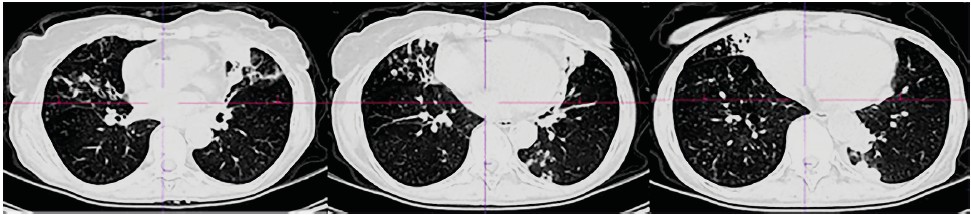

CT scans of the chest organs were performed repeatedly, where various dynamics were noted: migration of compaction areas, changes in their size and shape, changes in the shape and number of dilated bronchi. In general, the dynamics are negative, with a slow increase in the severity of bronchiectasis, the number and size of compaction areas (Table 1, Fig. 1–3).

Fig.2. Computed tomography of the chest organs of patient R dated 06/20/2023